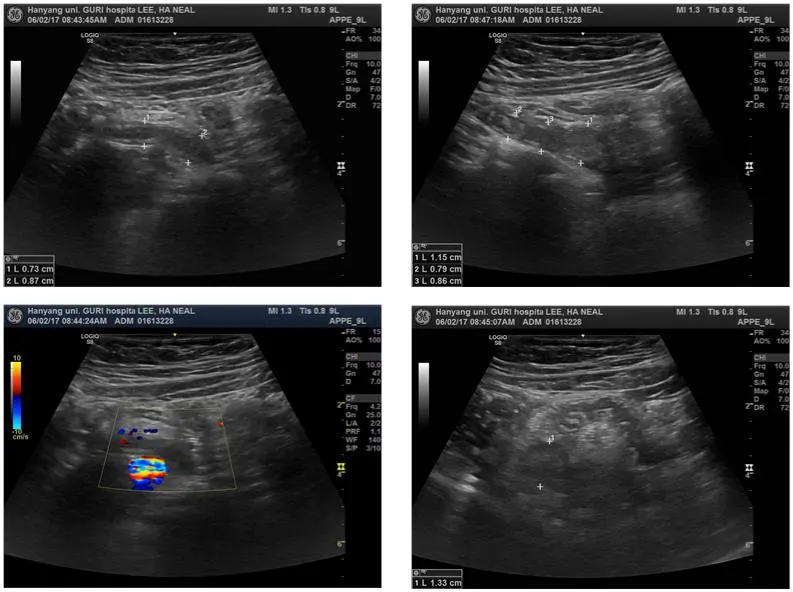

Tip Appendicitis

Inflammation localizing to the distal third portion of the appendix

Can be a cause for false-negative US diagnoses

Entire length of the appendix should be carefully evaluated in every case

이 환자는 appendicolith있고 tip 직경은 1.5cm. 01613228

Hyperemia

Hyperemia는 염증의 중요한 지표

염증있는 appendix wall은 color doppler에서 hypremic 하다

민감도 52%, 특이도 96%